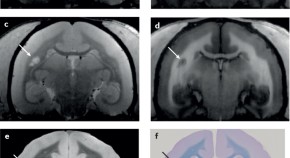

• MRI-based visualization of demyelinated CNS lesions is pivotal to the diagnosis and monitoring of multiple sclerosis (MS). The authors describe how advanced multimodal neuroimaging techniques are providing valuable insights into lesion structure and blood–brain barrier dynamics, thereby narrowing the gap between the macroscopic view of the radiologist and the microscopic view of the pathologist. The findings in humans are compared with data from a primate model of MS — experimental autoimmune encephalomyelitis in the common marmoset.

• Martina Absinta

• Pascal Sati

• Daniel S. Reich

Reviews

Nature Reviews Neurology

Volume: 12, P: 358-368